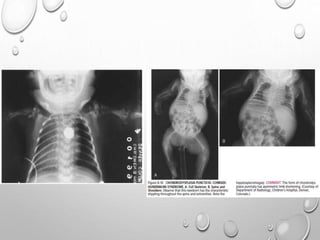

Chest radiograph in an infant demonstrates

overall increased density of osseous

structures due to accumulation of immature

Generalized increased density of bones &

alternating areas of increased & decreased

density in metaphyses (bone-within-bone

appearance).